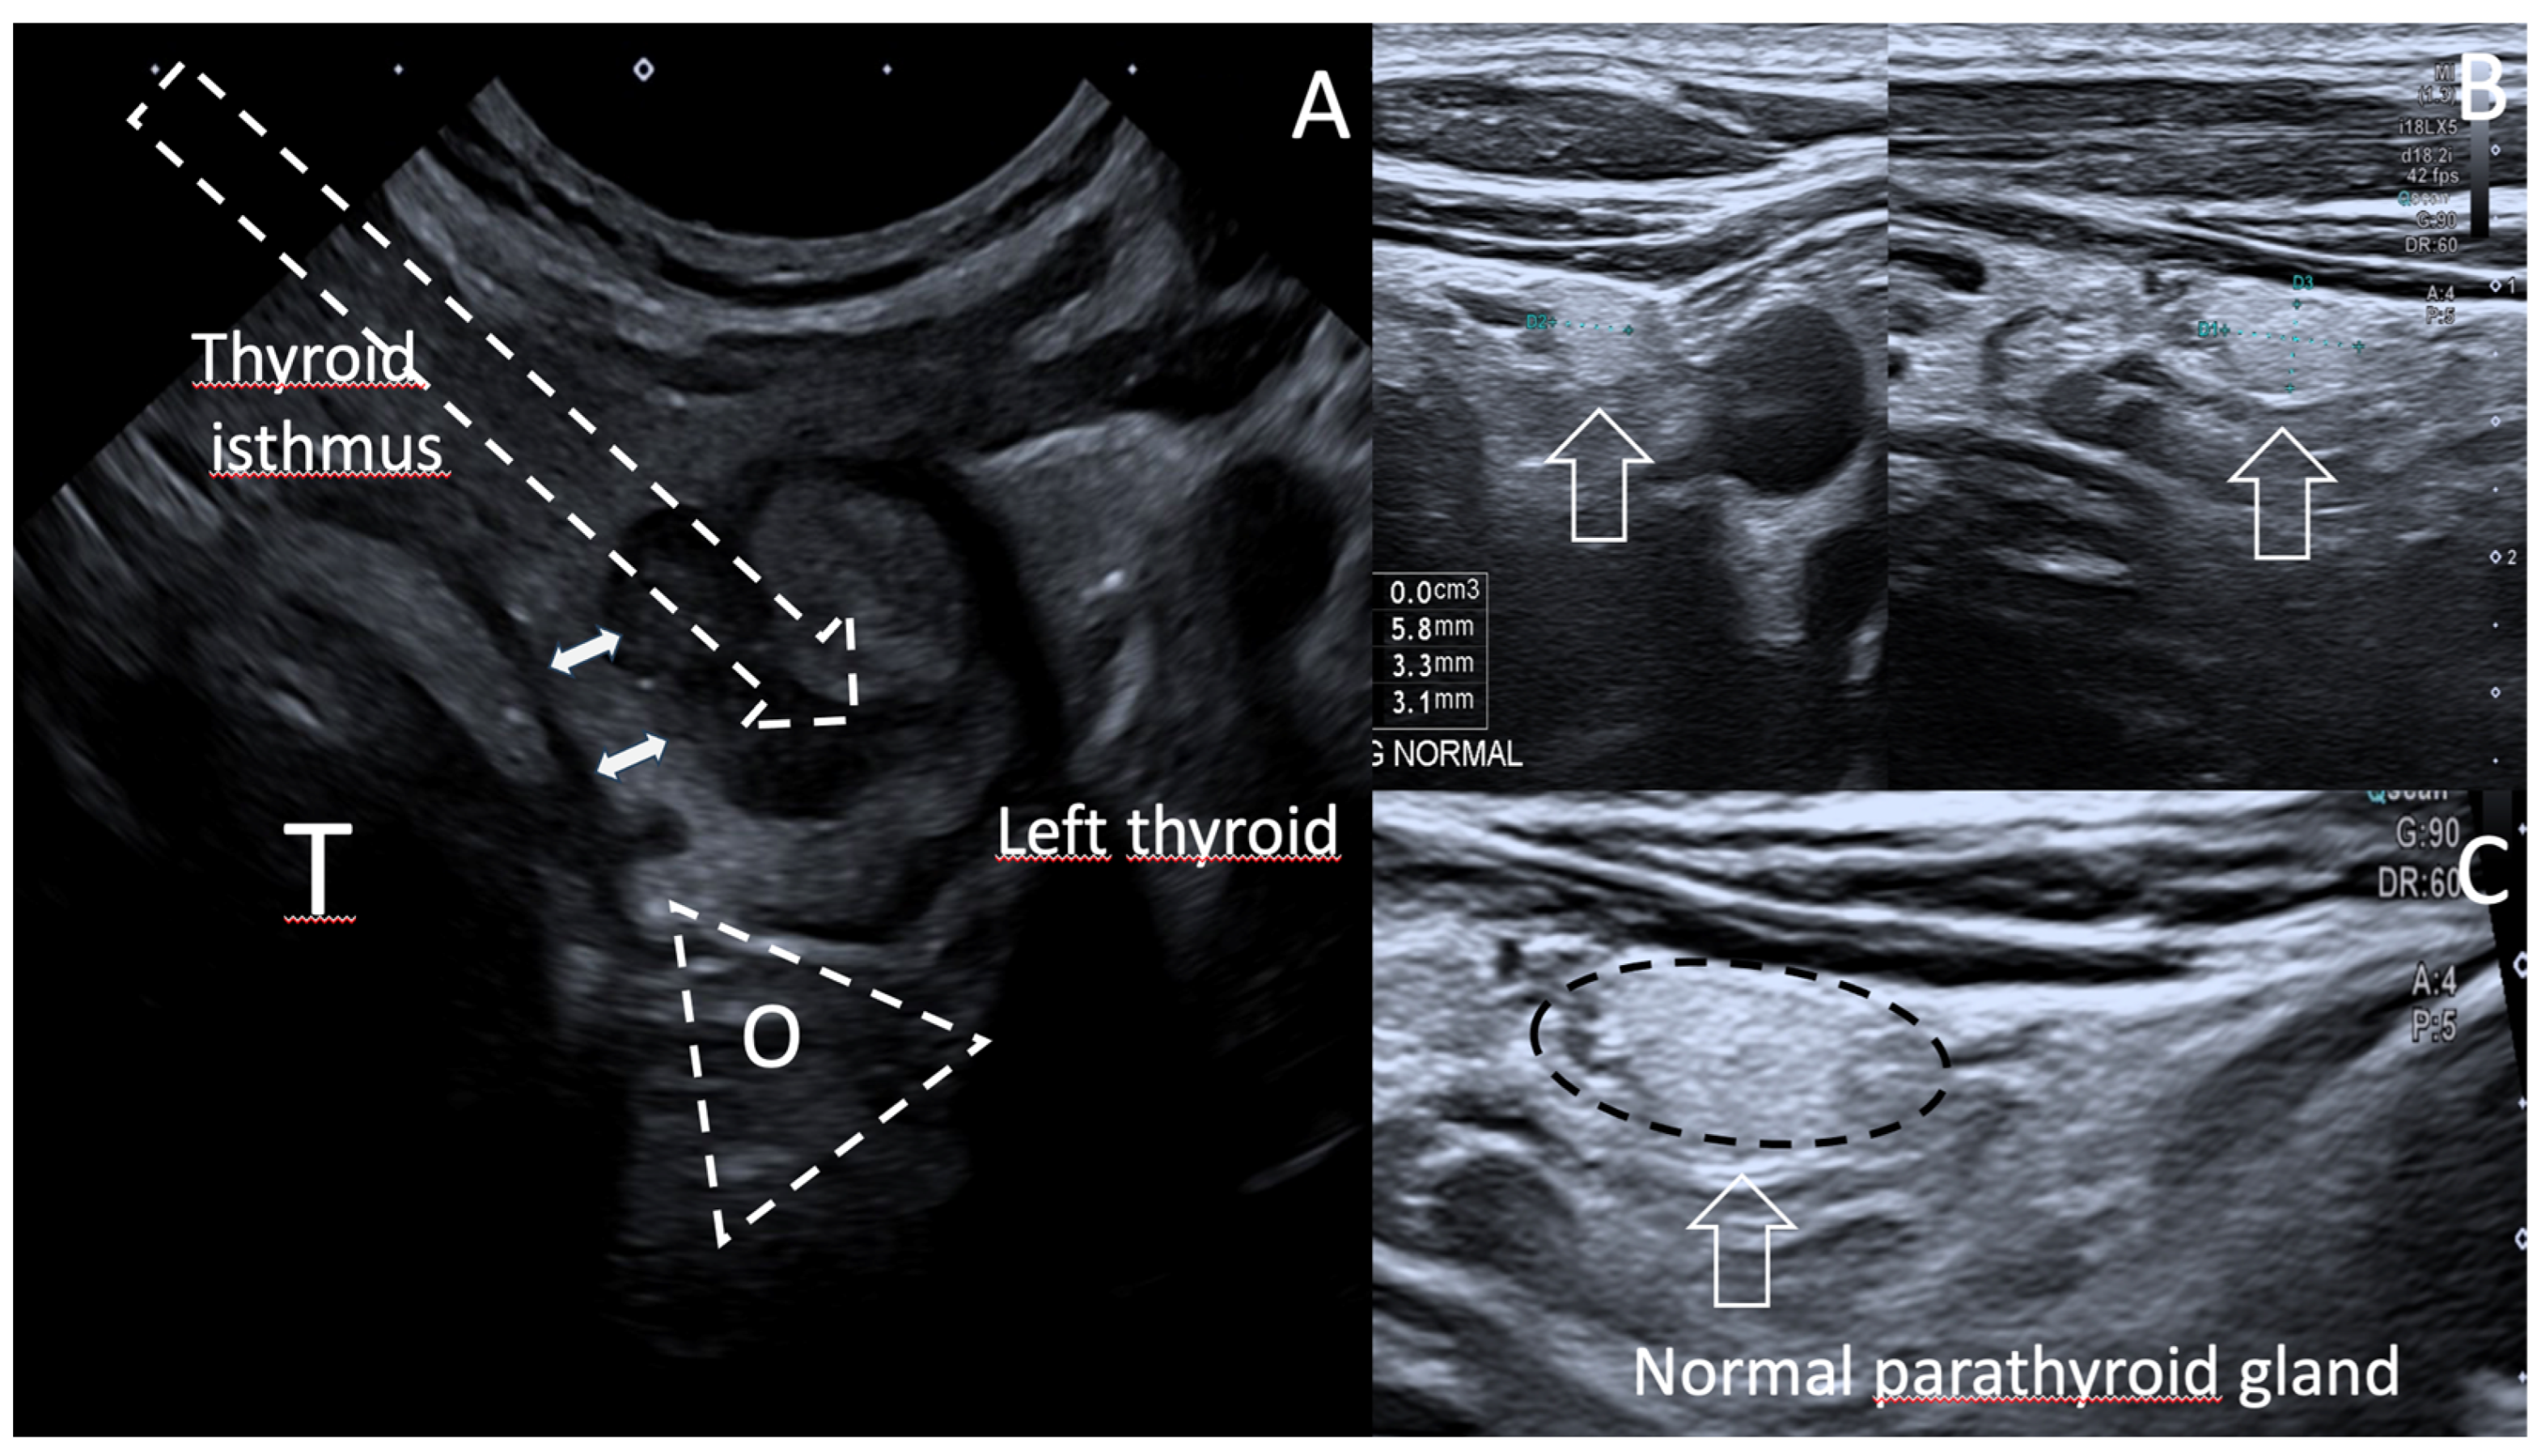

- Kim, S.J.; Na, D.G.; Noh, B.J. US features of normal parathyroid glands: A comparison with metastatic lymph nodes in thyroid cancer. Ultrasonography 2023, 42, 203–213. [Google Scholar] [CrossRef] [PubMed]